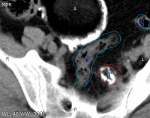

Женщина 65 лет поступила с острым корешковым синдромом справа и локальным отеком в/3 правого бедра. На рентгенограмме костей таза вот такая картина. Что это каловый камень или что то другое?

Моя теория невероятности). Вижу два образования. Одно из них, неправильной формы, расположенное кзади может быть каловым камнем. Второе, большее по размерам, округлой формы с обызвествленной стенкой, содержащее плотные включения, похожие на зубы, может быть тератодермоидной кистой яичника.

На вскрытии оказалась, как предполагала Наталия Ивановна, дермоидная киста размерами 15х8х5 см с кальцинированными стенками и клубком волос.

Был в патанатомии, киста однокамерная, с зубами, волосами и замазкобразным веществом, овальной формы 15х8х5 см. Второе образование не видели, ампулу прямой кишки не вскрывали.... жаль...

2 тератомы правого яичника.  Правую ягодичную и бедренную область "разнесло"

R-прямая,S-сигма, M-матка,T-образование. Слайды в каудально-краниальном направлении.  Тератома нижней своей частью прилегает к прямой кишке и давит на нее. Сигма интимно прилегает к образованию по задней поверхности ,  спокойно его огибает в верхней части по правому краю. Намеков на внутрикишечное положение нет.